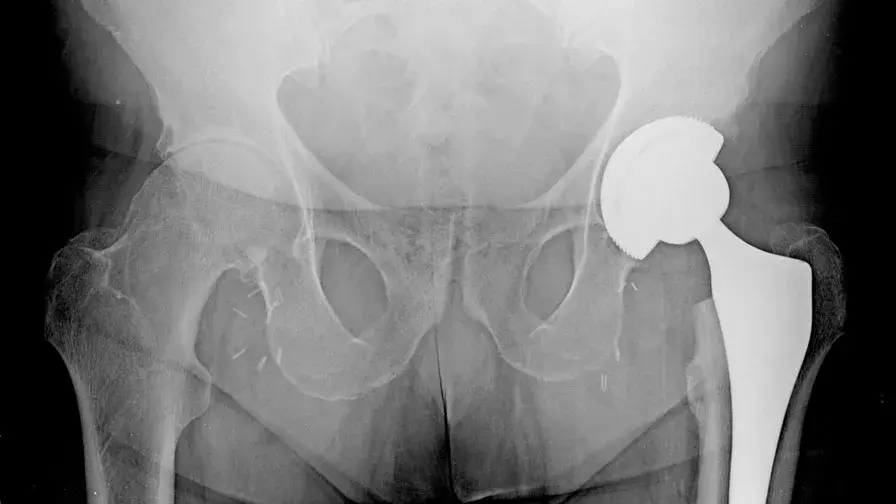

Des prothèses totales de hanche ont été posées en une journée avec retour à domicile le soir-même : une première à l’AP-HP.

• Des équipes de l’hôpital Cochin et de l’hôpital Ambroise-Paré ont récemment réalisé des poses de prothèse totale de hanche en ambulatoire, c'est-à-dire en moins de douze heures. Quelques heures seulement après ces interventions de "chirurgie lourde", les patients ont pu se lever, marcher et regagner leur domicile, où ils ont bénéficié d'un accompagnement adapté. Habituellement, la durée moyenne de séjour à l'hôpital des patients opérés pour ce type de prothèses était de 7 à 10 jours dans nos hôpitaux.